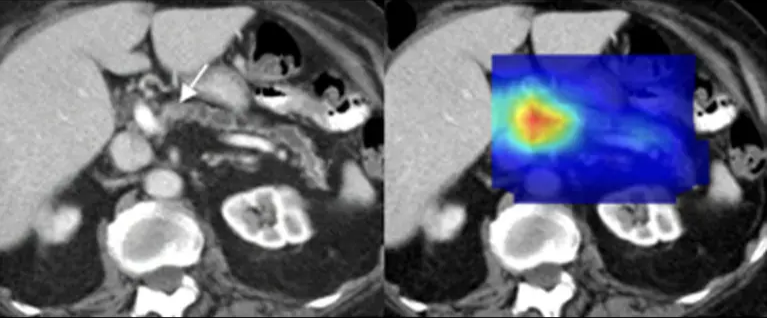

Medical imaging is one of the areas where artificial intelligence has delivered some of the most immediate and concrete results. A research group led by the Mayo Clinic demonstrated that AI models can detect early signs of pancreatic cancer in standard abdominal CT scans up to three years before clinical diagnosis. The system was trained on tens of thousands of patient scans, learning to identify subtle patterns that are often invisible to the human eye.

AI-assisted analysis of abdominal CT scans highlights microscopic pancreatic patterns, enabling cancer detection years before traditional diagnostic methods.

These systems rely on deep learning models specifically designed to “read” medical images. In practice, 2D and 3D convolutional neural networks (CNNs) are trained on large datasets of annotated CT scans to recognize complex morphological patterns at the pixel level, similar to how a radiologist works, but with much finer granularity. U-Net architectures are commonly used for semantic segmentation, allowing the model to automatically isolate potentially pathological regions. The output is not a simple yes/no classification, but heatmaps integrated into PACS systems that show where the model is focusing its attention. Performance is evaluated using screening-oriented metrics such as AUC, sensitivity, and false-negative rate, critical measures when the goal is early disease detection.